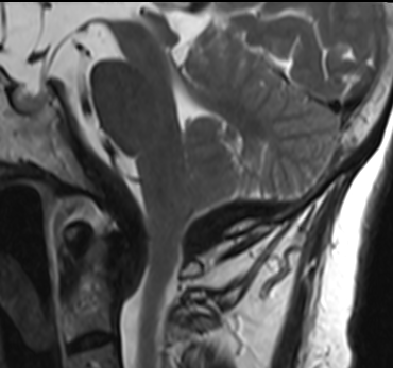

2015-4-1 MRI

2015-4-1